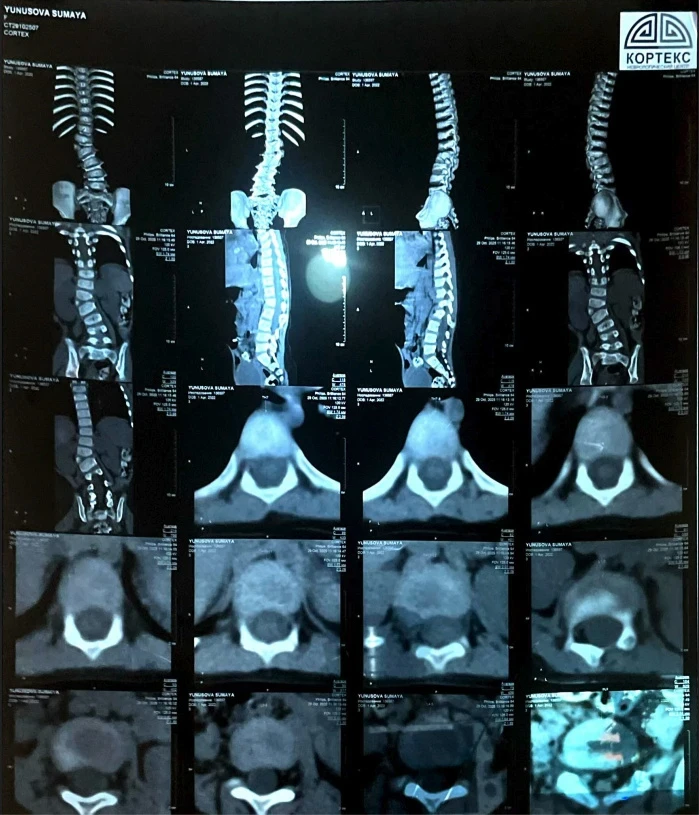

"Понимая, что лечение не помогает, мы обратились к специалистам из Турции. Они уверены, что единственным вариантом является операция, и чем быстрее она будет проведена, тем лучше для развития Сумаи. Недавно мы также узнали, что у нее есть лишняя кость на позвонке, что видно на рентгене, и это также связано с сколиозом", - рассказывает мама.

Из-за искривления позвоночника у Сумаи уже наблюдается асимметрия тела: одно плечо ниже другого, а одна нога короче.